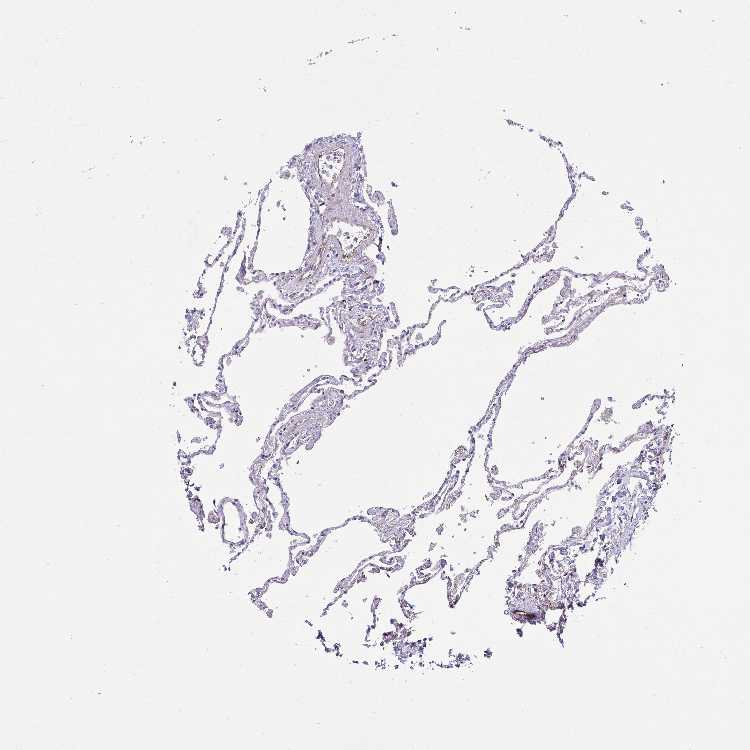

LUNG - Antibody stainingi

Antibody staining in the annotated cell types in the current human tissue is reported as not detected, low, medium, or high, based on conventional immunohistochemistry profiling in selected tissues. This score is based on the combination of the staining intensity and fraction of stained cells.

Each image is clickable and will lead to virtual microscopy that enables deeper exploration of all samples and also displays staining intensity scores, fraction scores and subcellular localization as well as patient and tissue information for each sample.

Antibody HPA057763

Alveolar cells Not detected

Macrophages Low